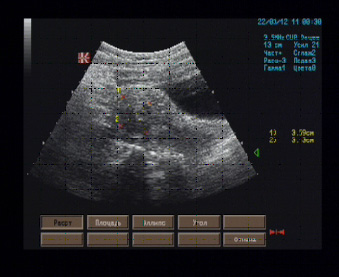

Матка размерами 74 х 69 х 44 мм, anteflexio, грушевидной формы, типичного расположения, передний контур перешеечного отдела деформирован гипоэхогенным узловым образованием диаметром 16 мм, двумя третями располагающимся в миометрии, имеющим однородное внутреннее строение, четкие границы в виде гиперэхогенной капсулы толщиной до 1 мм; в проекции полости тела матки визуализируется гипоэхогенная структура размерами 32 х 30 х 20 мм, имеющая четкие волнистые контуры, жидкостную полость в центра диаметром 9 мм, напоминающую наполненную жидким содержимым полость тела матки; на остальном протяжении миометрий изоэхогенный, однородный, эндометрий толщиной 7 мм, изоэхогенный, просвет свободен от дополнительных эхоструктур.

Эхографические признаки интрамуральной миомы передней стенки перешеечного отдела матки, субмукозной миомы тела матки (дифференцировать с зоной воспаления вокруг расширенной полости матки).